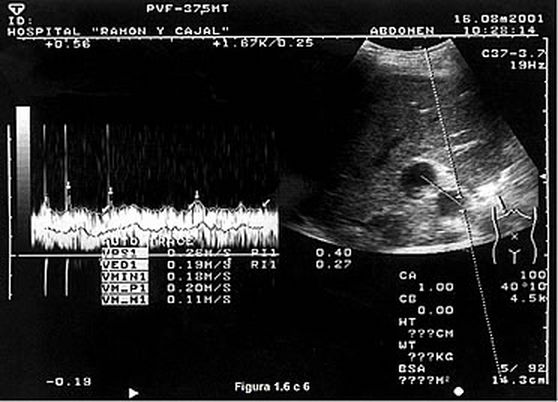

Trombosis arterial. Estenosis arterial Los hallazgos Doppler son aumento de la velocidad a niel de la estenosis (200-300 cm/sg) y turbulencia distal a ésta; sin embargo, en la mayoría de los pacientes no se puede encontrar el lugar de la estenosis y el diagnóstico se basa en el hallazgo de un pulso 'Tardus et Parvus' (Índice de resistencia <0,5. Tiempo de aceleración sistólica > 0,1) en arterias intrahepáticas distales a la estenosis (sensibilidad y especificidad del 73%) |